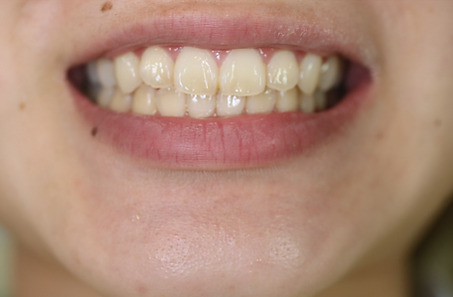

2ホワイトニング【治療例3】

治療前

治療後